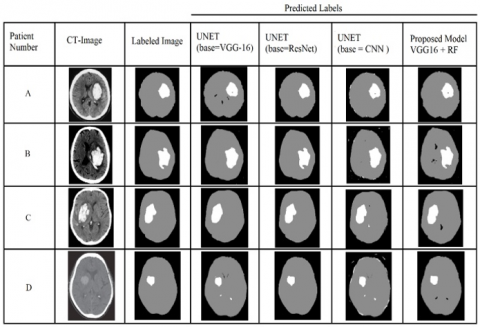

Figure 9 shows the pre-processed brain CT images of 8 patients, in which 6 patients are affected with stroke and remaining 2 are non-stroke patients. Figure 10 shows the labeled brain CT images of 8 patients. These labeled images contain three classes represented with white, gray, and black colors. Patients 4&8 are not affected with stroke, so these images are labeled with only two classes. The images shown in Figure 11 are predicted by our proposed model. Figure 12 shows output images of our proposed stroke segmentation on brain CT images.

Figure 13 shows an amalgam of multiple predicted labels alongside their patient numbers. It is clearly evident from the figure that U-Net with base ResNet gives highly accurate segmentation filters but takes the highest time for the whole prediction. The time taken by these models is shown in Table 2. In order to reduce the training time, we use U-Net with base VGG-16 and simple Convolutional neural network model. But this model also requires extremely high computational power, which is practically impossible for regular computers. Our model can approximately achieve the same results as these segmentation models and the dice coefficient values shown in Table 3. But with exponentially less computation power than U-Net that is, it can process and predict with a regular CPU also.

Figure 11. Predicted filter images of stroke and non-stroke patients

Table 3 shows the Dice coefficients of each algorithm with different input images are shown. Similarly the time taken by the algorithm is proportional to the number of convolutions. The dice coefficients of the algorithms are also proportional to the number of Convolutions. Since with increase in convolutions also increases the feature extraction ability. But in our proposed model the use of Random Forest algorithm to support the VGG-16 model is to increase the feature extraction ability without increase in the number of Convolutions. So the U-Net with base as ResNet has highest average of Dice Coefficients as it has highest number of convolutions, followed by our proposed model. Both U-Net with base VGG and U-Net with base CNN have less average dice coefficient values as they both contains less number of convolution.

Figure 13. Comparison results of existing models with proposed model